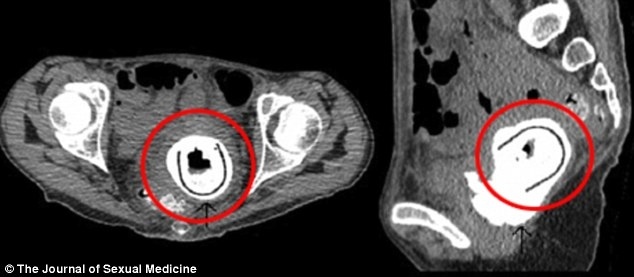

Οι γιατροί έμειναν έκπληκτοι όταν είδαν ότι ένα ξένο σώμα εξείχε στην κύστη της και προερχόταν από τον κόλπο της.

Η επέμβαση αποκάλυψε ότι ήταν ένα ερωτικό παιχνίδι μήκους 11 εκατοστών !

Η γυναίκα έπασχε από «κυστο-κολπικά συρίγγιο» - μια ανωμαλία που επιτρέπει τη ροή των ούρων μέσα στον κόλπο.

Είχε επίσης μια αποφρακτική ουροπάθεια, αφού είχε μπλοκαριστεί η ουροδόχος κύστη .